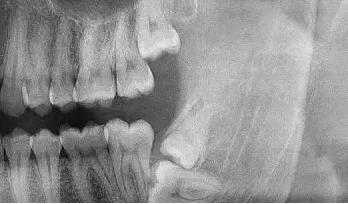

5、邻牙及支持组织的吸收:当阻生的智齿萌出过程中受阻于第二磨牙时,会引发第二磨牙牙根牙根逐渐吸收,严重者可使下颌第二磨牙远中牙根完全吸收,致第二磨牙松动、疼痛,常常食物嵌塞发生慢性牙周炎,也会造成牙槽骨的炎症性吸收,使第二磨牙反复肿痛。